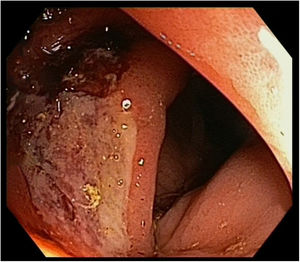

A follow-up CT scan 10 months after diagnosis showed mural thickening of the ascending colon (Fig. 1). A colonoscopy was performed and a superficial ulcer of non-specific appearance was observed in the right colon (Fig. 2). Histopathology was consistent with colonic metastasis of lung squamous cell carcinoma (Fig. 3).